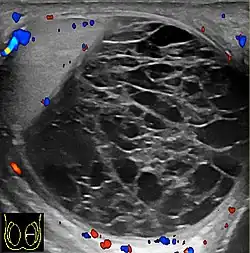

Teratoma Although teratoma is the second most common testicular tumor in children, it affects all age groups. Mature teratoma in children is often benign, but teratoma in adults, regardless of age, should be considered malignant. Teratomas are composed of all three germ cell layers, i.e. endoderm, mesoderm and ectoderm. At ultrasound, teratomas generally form well-circumscribed complex masses. Echogenic foci representing calcification, cartilage, immature bone and fibrosis are commonly seen [Fig. 5]. Cysts are also a common feature and depending on the contents of the cysts i.e. serous, mucoid or keratinous fluid, it may present as anechoic or complex structure [Fig. 6].

Fig. 5. Teratoma. A plaque-like calcification with acoustic shadow is seen in the testis. -

Fig. 6. Mature cystic teratoma. (a) Composite Image. Mature cystic teratoma in a 29-year-old man. Longitudinal sonography image of the right testis shows a multilocular cystic mass. (b) Mature cystic teratoma in a 6-year-old boy. Longitudinal sonography of the right testis shows a cystic mass containing calcification with no obvious acoustic shadow.